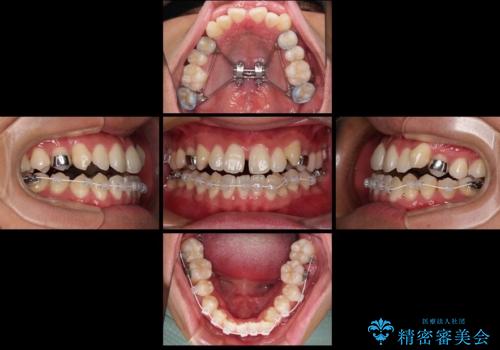

上顎の急速拡大装置を使用して、上顎骨を側方に拡大することで上顎歯列弓を拡大し、それに伴い下顎歯列弓も拡大できるようにして、歯列を整えていくこととしました。

- 矯正装置

- 審美装置